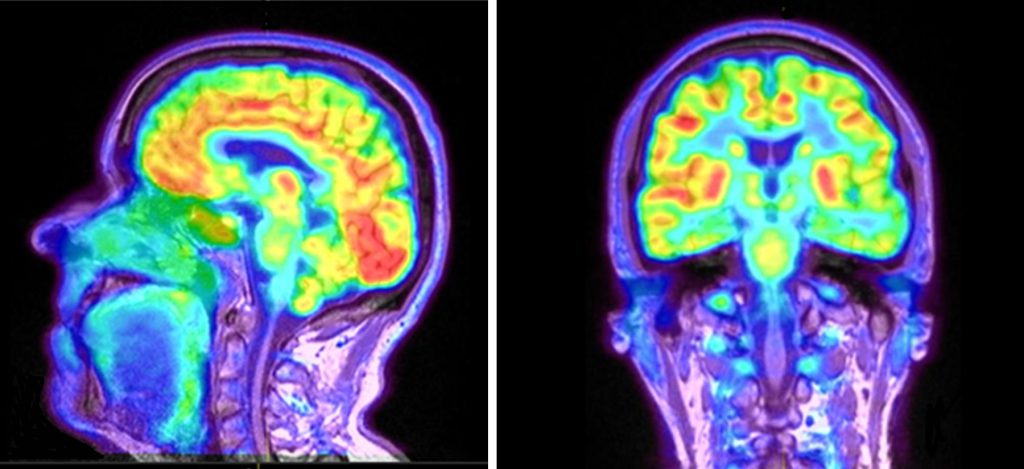

پت اسکن یا توموگرافی با گسیل پوزیترون (PET Scan)، یکی از پیشرفته ترین روش های تصویر برداری پزشکی است که با استفاده از مواد رادیواکتیو، فعالیت های متابولیکی بدن مانند جریان خون، سوخت و ساز سلول ها و عملکرد اندام ها را نشان می دهد.

برخلاف روش های ساختاری مثل MRI یا سی تی اسکن، پت اسکن عملکرد اندام ها را به تصویر می کشد و به پزشکان این امکان را می دهد تا سرطان، اختلالات مغزی، بیماری های قلبی یا عفونت های پنهان را با دقت بالا تشخیص دهند.

برای انجام پت اسکن، بیمار ابتدا ماده ای به نام FDG (نوعی گلوکز رادیواکتیو) دریافت می کند و پس از جذب این ماده توسط بافت های بدن، تصویر برداری انجام میشود. این تکنولوژی فقط در مراکز تخصصی پزشکی هسته ای در دسترس است.